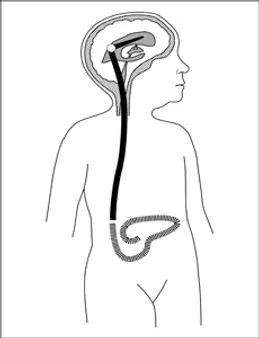

Şant implantasyonu. Hidrosefalide en sık uygulanan tedavi yöntemidir. Şant adı verilen bir drenaj sistemi cerrahi olarak yerleştirilir. Uzun, ince bir tüp şeklinde, fleksibl valv yapısına sahip olan bu sistem; sıvının beyinden doğru yönde, doğru oran ve miktarda akışını sağlar. Şantın bir ucu beynin ventrikülüne yerleştirilir. Drenaj sistemi ciltin altından fasya üzerinden bir tünel oluşturulduktan sonra diğer ucu beyinden gelen sıvının emilebileceği karın boşluğu, kalp gibi bir vücut boşluğuna yerleştirilir.

Hidrosefalisi olan bir çocuğa şant yerleştirilmesini takiben hayatının geri kalanında hastanın büyümesi nedeniyle şantın uzatılması yada şantta tıkanma, enfeksiyon gelişmesi nedeniyle revizyon gibi ek cerrahilere gereksinim duyabilir.